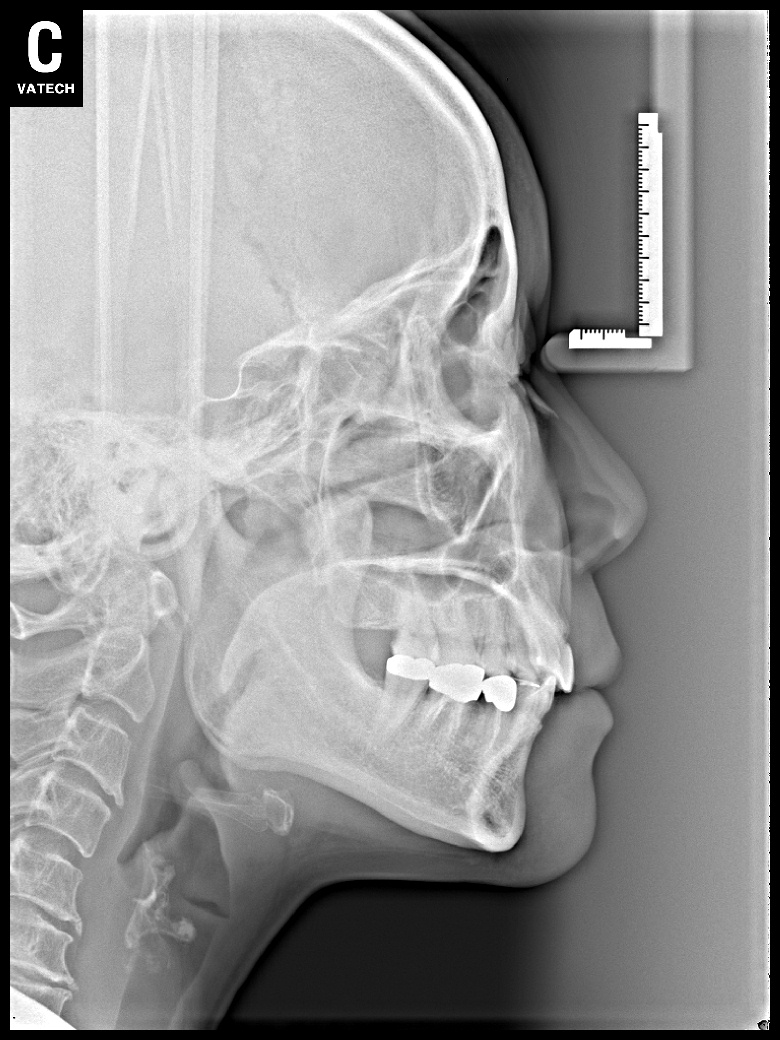

치료 전 사진입니다.